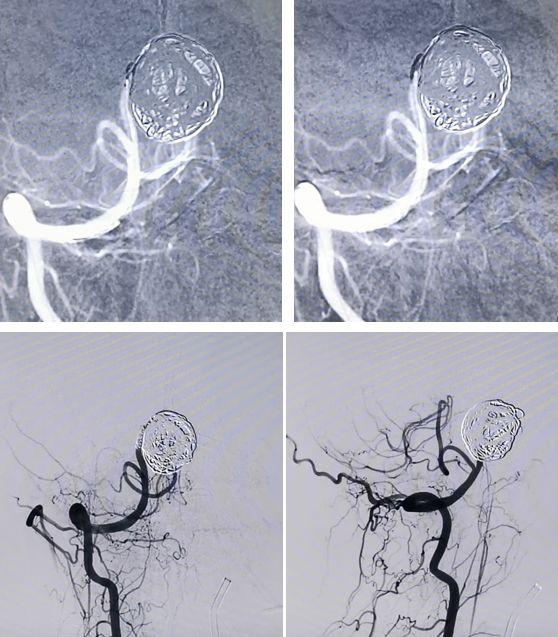

PED释放完毕,位置及贴壁良好,左椎-基底动脉血运通畅,未填弹簧圈,即可见到瘤腔内造影剂的滞留,说明支架贴壁良好,起到了良好的重建作用

经右椎动脉逐步填塞大弹簧圈进入动脉瘤(Microplex-18系列),逐步将动脉瘤疏松填塞。期间微导管头端受到弹簧圈阻力,会缓慢回撤,此时不必刻意调整微导管再次深入动脉瘤腔内,因为我们最主要目的不是严密填塞动脉瘤—那是PED的任务—而是闭塞右侧椎动脉

最后,用小弹簧圈完全闭塞右侧椎动脉(PICA以远)

左椎动脉造影显示椎-基底动脉及远端血管通畅,动脉瘤虽然部分显影,但是PED最终会让动脉瘤完全修复。